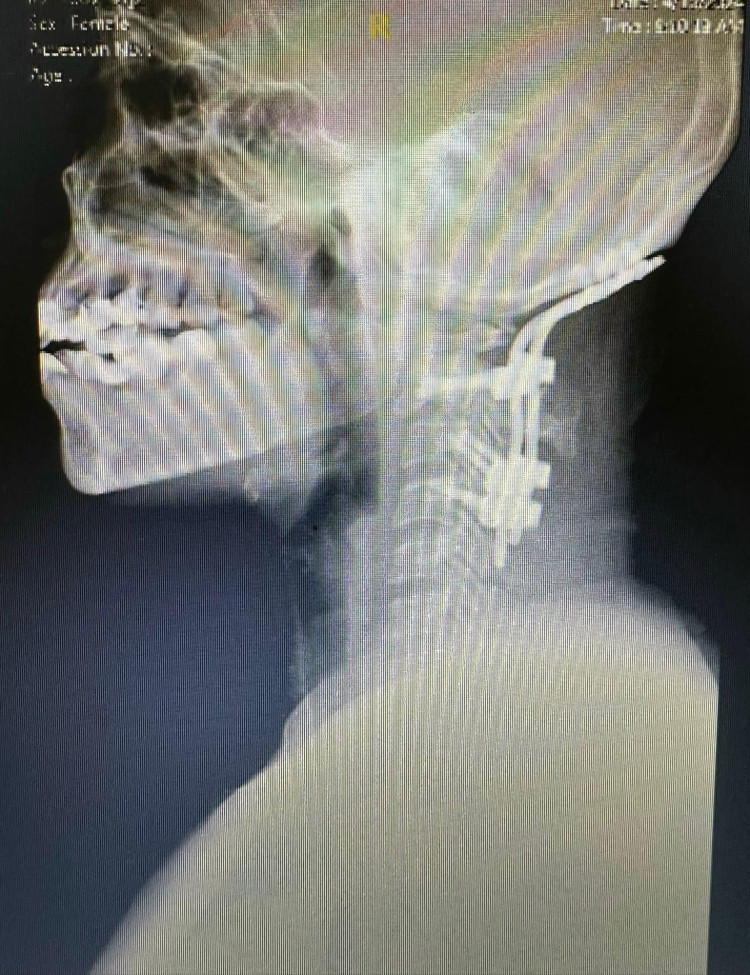

| Phẫu thuật nắn chỉnh và cố định cột sống cổ và xương sọ |

Ngày 12/4, các bác sỹ khoa Ngoại thần kinh TS.BS Nguyễn Đức Liên, Trưởng khoa và Ths.Bs Nguyễn Thái Học, Ths.Bs Nguyễn Văn Linh đã tiến hành phẫu thuật, ca mổ được chuẩn bị chu đáo từ việc kê tư thế, bởi chỉ cần cúi cổ hoặc ưỡn cổ quá mức cũng có thể làm tổn thương tủy.

Các bác sỹ đã thực hiện các thao tác rất cẩn thận, can thiệp giải ép tủy sống khỏi chèn ép trước, sau đó nắn chỉnh và cố định cột sống cổ và xương sọ. Sau mổ 4 ngày người bệnh bắt đầu tập ngồi dậy và tập đi lại, có thể chỉ định dùng thuốc hóa chất duy trì sau 2-3 tuần.